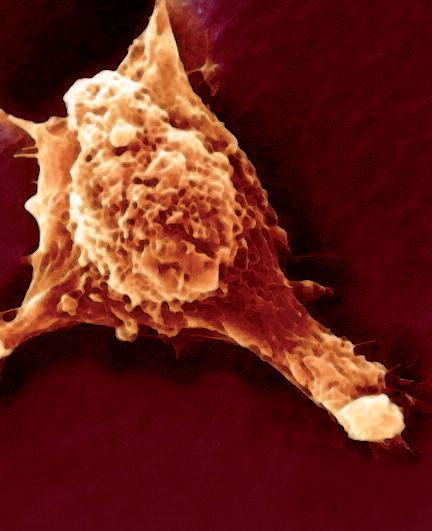

La pagina a fianco mostra l'immagine di una cellula tumorale reale, visualizzata al microscopio elettronico, che ingrandisce questa cellula 6500 volte rispetto alle sue normali dimensioni. Questo tipo di cellula prende il nome di carcinoma, cioè derivante da cellule epiteliali, il tipo di cellule che rivestono sia le superfici interne (polmoni, intestini) che esterne (pelle) del corpo.

Grazie a questo ingrandimento si possono identificare chiaramente alcune delle caratteristiche di tutte le cellule tumorali: a) l'enorme nucleo cellulare dalla forma insolita che spiega la loro grande capacità di riprodursi e b) la struttura non uniforme, complessa della superficie cellulare, che riflette una forte attività di secrezione di sostanze prodotte dalle cellule tumorali.

Una delle più importanti molecole secrete dalle cellule tumorali in grandi quantità sono gli enzimi a ‘forbice’ che digeriscono il collagene. Sono aggiunti graficamente a questa immagine, sotto forma di strutture simili ad un ‘pacman’ rosso.

La foto nella pagina a fianco mostra una cellula cancerogena ad un microscopio.

Il corpo di questa cellula tumorale in migrazione si espande nella direzione del suo movimento all’interno del tessuto. Può formare una struttura ‘tentacolare’ che trascina la cellula tumorale lungo la superficie, in questo caso, di un vaso sanguigno.

Gli enzimi che digeriscono il collagene sono aggiunti per illustrare il processo mediante il quale qualsiasi ostacolo sul cammino di questa cellula tumorale viene superato.